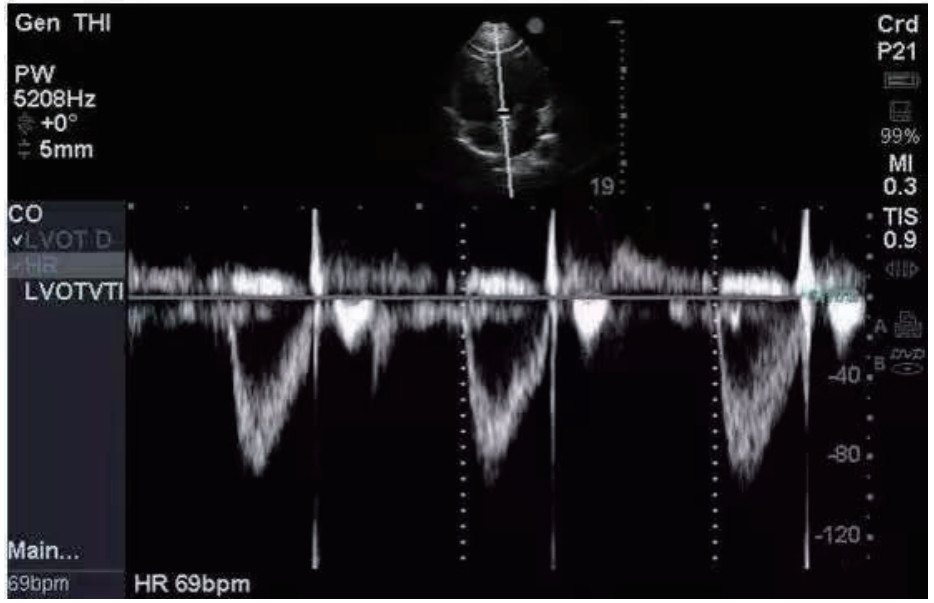

1.2 方法 1.2.1 资料收集通过查阅电子病历收集CCS患者年龄、性别、是否合并高血压和(或)糖尿病等基础病、急诊入院时头颅CT影像学表现、GCS评分、急性生理学与慢性健康状况评分Ⅱ(APACHE Ⅱ)等基本资料,以及急诊入院后电解质(钾、钠),血液检查指标C反应蛋白(CRP)、葡萄糖(GLU)、肌酸激酶(CK)、肌酸磷酸激酶同工酶(CKMB)、乳酸脱氢酶(LDH)、神经元特异度烯醇化酶(NSE),手术后转入ICU监测床边心脏彩超指标:速度时间积分(VTI)(见图 1)、射血分数(EF),右心Tei指数,术后颅内压(ICP)及相应时间的视神经鞘直径(ONSD),记录术后第3天ICP,并计算ICP变化率=(术后ICP-术后第3天ICP)/术后ICP等临床资料,记录两组患者转入ICU是否使用血管活性药物及用量(重酒石酸去甲肾上腺素注射液生产厂家:远大医药(中国)有限公司,批准文号:国药准字H42021301,规格:2 mg/支),镇静镇痛等治疗用量及平均每日液体平衡量等指标,其中镇痛药物使用注射用盐酸瑞芬太尼(生产厂家:宜昌人福药业有限责任,批准文号:国药准字H20030197,规格:1 mg/瓶),镇静药物为丙泊酚注射液(生产厂家:西安力邦制药有限公司,批准文号:国药准字H19990282,规格0.2 g/支)。心脏彩超及ONSD测量均为本院通过重症超声规范化培训并取得合格证书者完成,心脏彩超测量采用EDGE型彩色多普勒超声仪(美国索诺声公司)检测,其中Tei指数是由多普勒超声衍生而出的时间间期指数,定义为等容收缩时间(ICT)与等容舒张时间(IRT)之和除以射血时间(ET)。Tei指数的计算公式:Tei指数=(ICT+IRT)/ET。连续测量3次取平均数。ONSD采用EDGE型彩色多普勒超声仪(美国索诺声公司)高频(5.0~10.5 MHz)线阵超声探头测量眼球后3 mm位置视神经鞘的宽度,并反复测量3次取平均值(见图 2)。

| 图 1 VTI测量 Fig 1 VTI measurement |